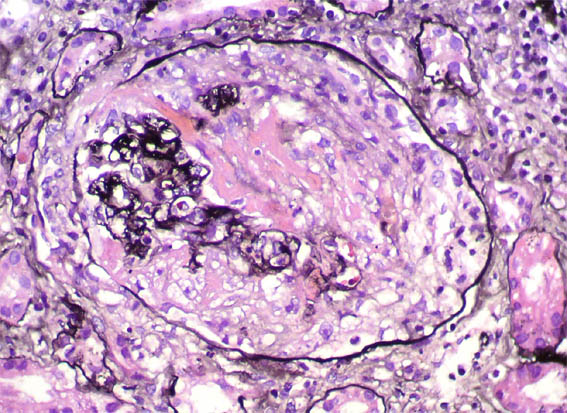

Figura 2. H&E, X400.